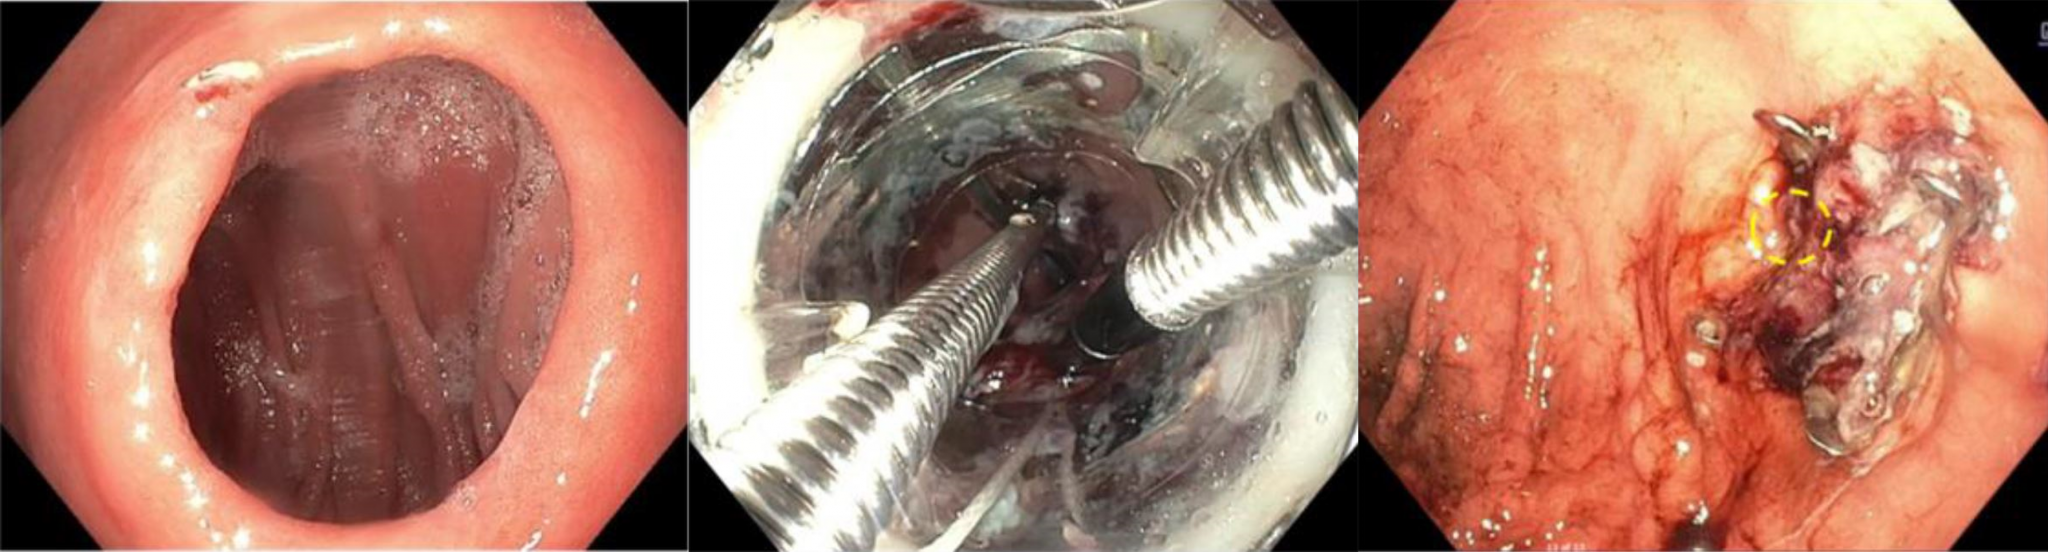

Case example: First U.S. BARS® experience3

A 52-year-old female patient presented after bypass (RYGB in 2009) with 67.3% weight regain. Her enlarged gastrojejunal anastomosis was successfully treated with BARS® in a single endoscopic session.

Endoscopic view of the anastomosis before (20 mm), during and after BARS® treatment (5 mm).3

Key results:

- Anastomotic reduction: 20 mm → 5 mm (75% reduction)

- Weight loss at 1 month: 12.2 kg (13.5% TBWL)

- BMI reduction: 40.5 → 36.0 kg/m² (-4.5 kg/m²)

The procedure was completed in 48 minutes with no adverse events reported. The authors reported a steep learning curve, with procedure time decreasing to 19 minutes by case 3, suggesting BARS® can become a rapid ~20-minute procedure with operator experience.